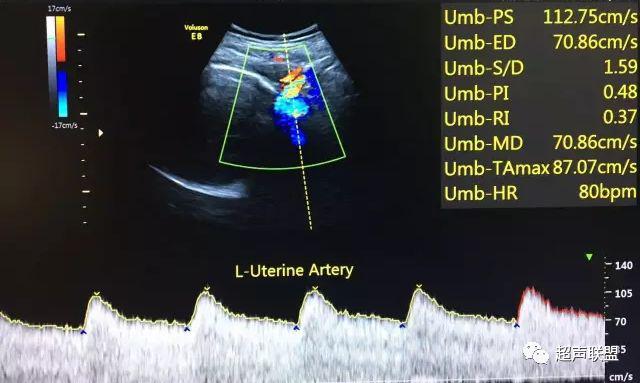

5 子宫动脉血流测定

正常妊娠时血流速度增加,血流阻力下降。缺氧早期的血流再分配,子宫动脉血流RI、PI值增加,阻力指数(RI)>0.57,子宫动脉血流频谱出现切迹。

3、子宫动脉标准:孕26或27周后,子宫动脉S/D>2.7,(RI)>0.57,有舒张早期切迹;

图7 正常中孕期子宫动脉频谱

图8 胎儿宫内缺氧,子宫动脉舒张早期可见切迹